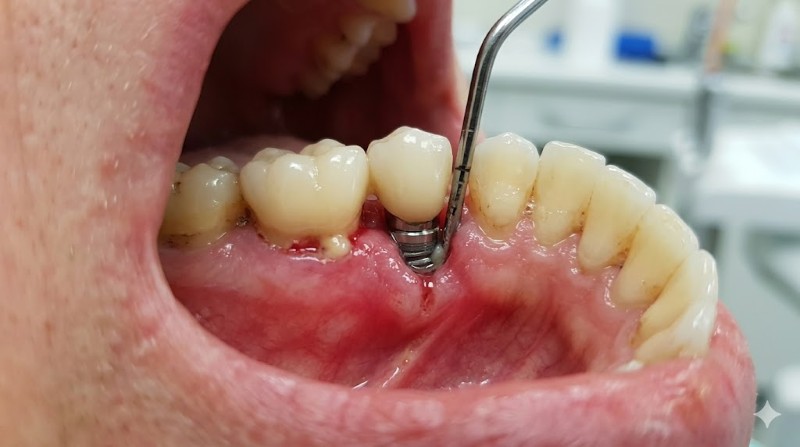

Nhiễm trùng vùng cấy ghép

Nhiễm trùng là một trong những biến chứng đầu tiên và phổ biến nhất khi trồng răng implant. Khi vùng cấy ghép không được giữ sạch sẽ, vi khuẩn có cơ hội xâm nhập dẫn đến nhiễm trùng. Khi bị nhiễm trùng, bệnh nhân sẽ cảm thấy đau nhức, sưng tấy và có thể kèm theo sốt. Nhiễm trùng nếu không được điều trị kịp thời có thể dẫn đến việc trụ implant không tích hợp với xương hàm, làm mất đi chức năng của nó.

Ngoài ra, việc nhiễm trùng còn có thể làm cản trở quá trình lành thương của mô mềm xung quanh, dẫn đến tình trạng viêm nhiễm kéo dài. Điều này không chỉ gây đau đớn mà còn làm tăng nguy cơ phải tháo bỏ implant. Để hạn chế tình trạng này, bệnh nhân cần đảm bảo vệ sinh răng miệng tốt và tuân thủ các hướng dẫn chăm sóc sau phẫu thuật.